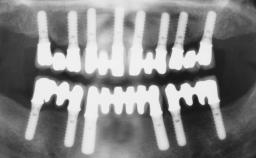

Conventional Loading of Eight Implants in the Maxilla and Final Restoration with a Full-Arch Gold-Ceramic FDP

A 35-year-old Caucasian female presenting with advanced periodontal disease involving both the maxillary and the mandibular dentition was referred for evaluation. The patient, a non-smoker in good general health, requested treatment for recurrent periodontal abscesses, tooth mobility, and discomfort during chewing, as well as restoration of her missing teeth with a fixed prosthesis to improve mastication and esthetics. All residual maxillary teeth exhibited plaque deposits, deep pockets, bleeding on probing, and class III mobility and were evaluated as hopeless. All residual mandibular teeth except tooth 37 could be maintained after periodontal therapy.

# of Implants 8